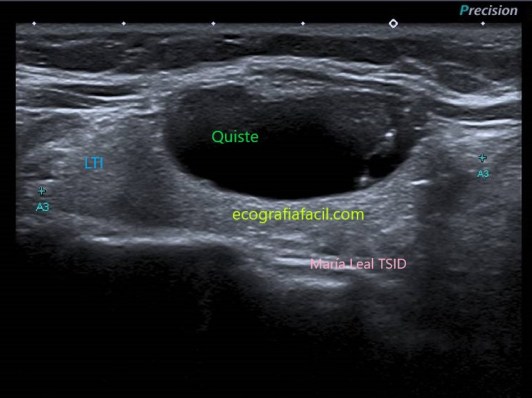

QUISTE:

Quiste

Los artefactos en “cola de cometa” son focos ecogénicos con forma en “V”. Se asocian con contenido coloide y son muy indicativos de benignidad cuando se encuentran dentro de componentes quísticos en los nódulos tiroideos.